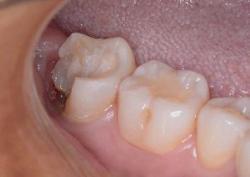

Метод выбирают по рентгеновскому снимку и осмотру. Врач учитывает форму корней, объем разрушения, состояние кости и мягких тканей. В практике применяются:

В зависимости от ситуации выполняют простое или сложное удаление. При сложном варианте зуб могут разделить на части, чтобы убрать его аккуратно и без лишней травмы.

Результат:

болевой синдром и отёк купированы, заживление прошло без осложнений, соседние зубы и костная ткань сохранены.